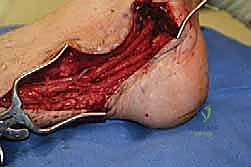

الخلاصة الطبية السريعة: التهاب الأعصاب الالتصاقي (Adhesive Neuritis) هو حالة طبية معقدة ومؤلمة للغاية، تنتج عن تندب الأعصاب الطرفية والتصاقها بالأنسجة الرخوة المحيطة بها، مما يفقدها القدرة على الانزلاق الطبيعي أثناء الحركة. تحدث هذه الحالة غالبًا كمضاعفات لجراحة سابقة، أو نتيجة صدمات وإصابات مباشرة. يتضمن بروتوكول العلاج المتقدم، والذي يقدمه الأستاذ الدكتور محمد هطيف في صنعاء، تحرير العصب جراحيًا بدقة ميكروسكوبية متناهية (Neurolysis)، مقترنًا بإجراءات حاجزية مبتكرة (Barrier Procedures) لتغليف العصب ومنع تكرار تكوّن الالتصاقات، مما يوفر راحة جذرية ودائمة للمرضى ويعيد لهم جودة الحياة.

يهدف نهجه الجراحي إلى تحرير هذه الأعصاب بدقة عالية باستخدام تقنيات الجراحة المجهرية، وفي كثير من الحالات، تطبيق "إجراءات حاجزية" (Barrier Procedures) مبتكرة لمنع عودة الالتصاقات مستقبلاً. يتطلب هذا النوع الدقيق من الجراحة صبرًا استثنائيًا، دقة متناهية، أمانة طبية صارمة، وفهمًا عميقًا للتشريح الإقليمي الدقيق للطرف السفلي، وهي السمات المهنية التي تميز مسيرة الأستاذ الدكتور محمد هطيف.